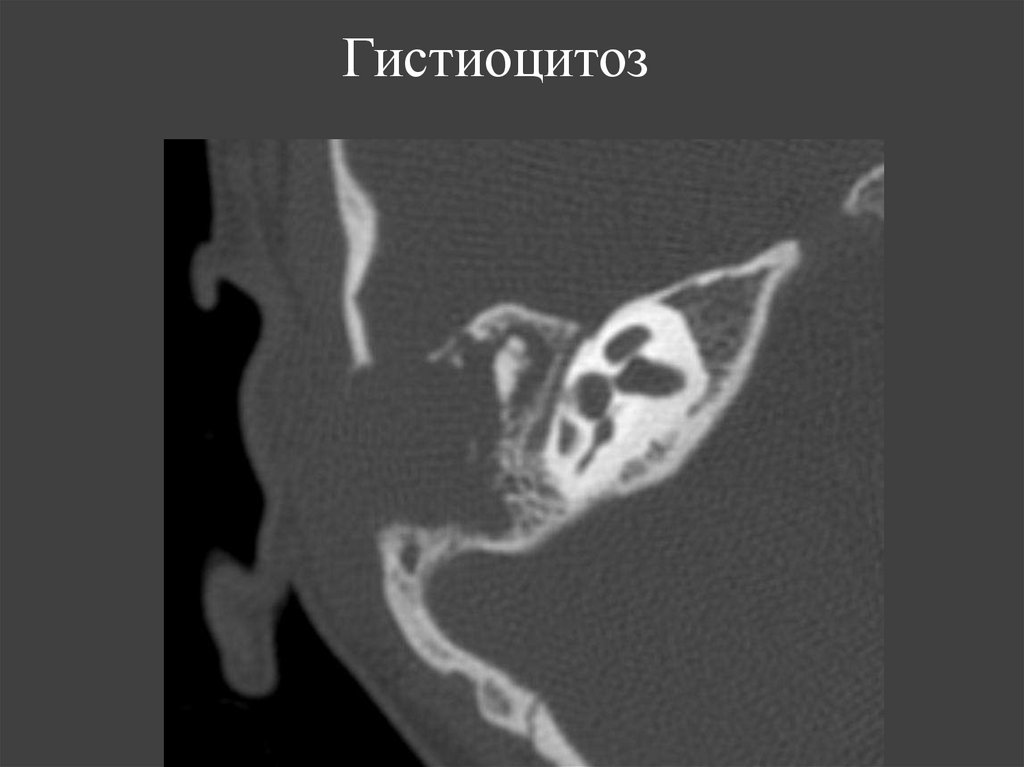

119. Гистиоцитоз

Параллельно длинной оси

ГИСТИОЦИТОЗЫ

МЕТАСТАТИЧЕСКОЕ

ПОРАЖЕНИЕ

Болезнь Леттерера-Сиве

Болезнь Хенда-ШюллераКрисчена

Эозинофильная гранулема

Деструкция костной ткани с

неровными контурами